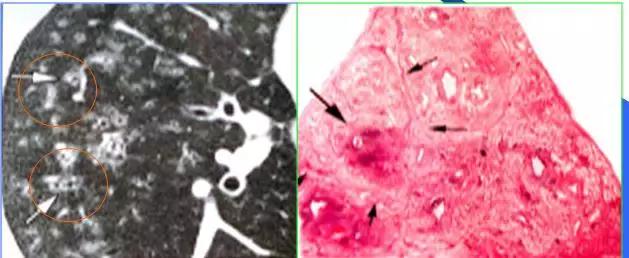

CT征象一:树芽征

由终末细支气管和肺泡腔内病变形成的小结节影与分支细线影构成的酷似春天的树枝发芽状,称“树芽征”(tree-in-bud)

CT表现:多在肺外围支气管末梢呈2-4mm大小结节与树枝状的高密度影。

意义:多表明有小气道病变如:细支气管炎症、弥漫泛发性细支气管炎及肺结核病灶或播散等

末梢细支气管扩张形成粘液栓——酷似“树芽征”

末梢细支气管与肺泡结核灶及播散——酷似“树芽征”

弥漫性肺小叶中心炎症——HE小叶间隔及小叶支气管周围浸润

末梢细支气管感染——HRCT与HE病理切片图显示“树芽征”

“树芽征”:活动性肺结核支气管播散;泛细支气管炎